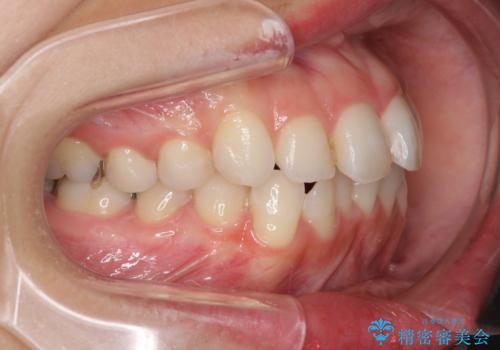

【モニター】前歯のデコボコをインビザラインできれいに整える

- 前歯のデコボコを気にして来院された患者様です。

主に下顎歯列全体の後方移動とIPR(歯と歯の間を削る)によってデコボコが解消するように設計し、インビザラインにより治療を行うこととしました。

舌突出癖がある方ですと、叢生が解消すると同時に前方に拡大されてしまいますが、ゴムかけをしっかりと行ってくださったこともあり、スッキリとした仕上がりとなりました。